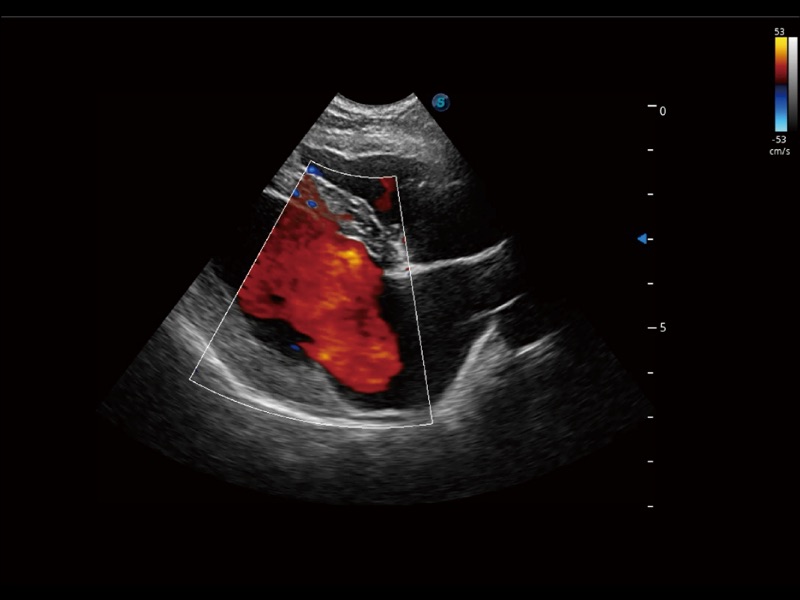

优异的基础图像

ProPet 70 全新的动物超声智能软件和丰富的探头群,为动物医生提供了高清晰度和精细分辨率的图像,无论在宠物、马科、畜牧还是实验室动物等应用中都可以轻松应对,为您的日常工作带来满意的体验。

(犬)四腔心